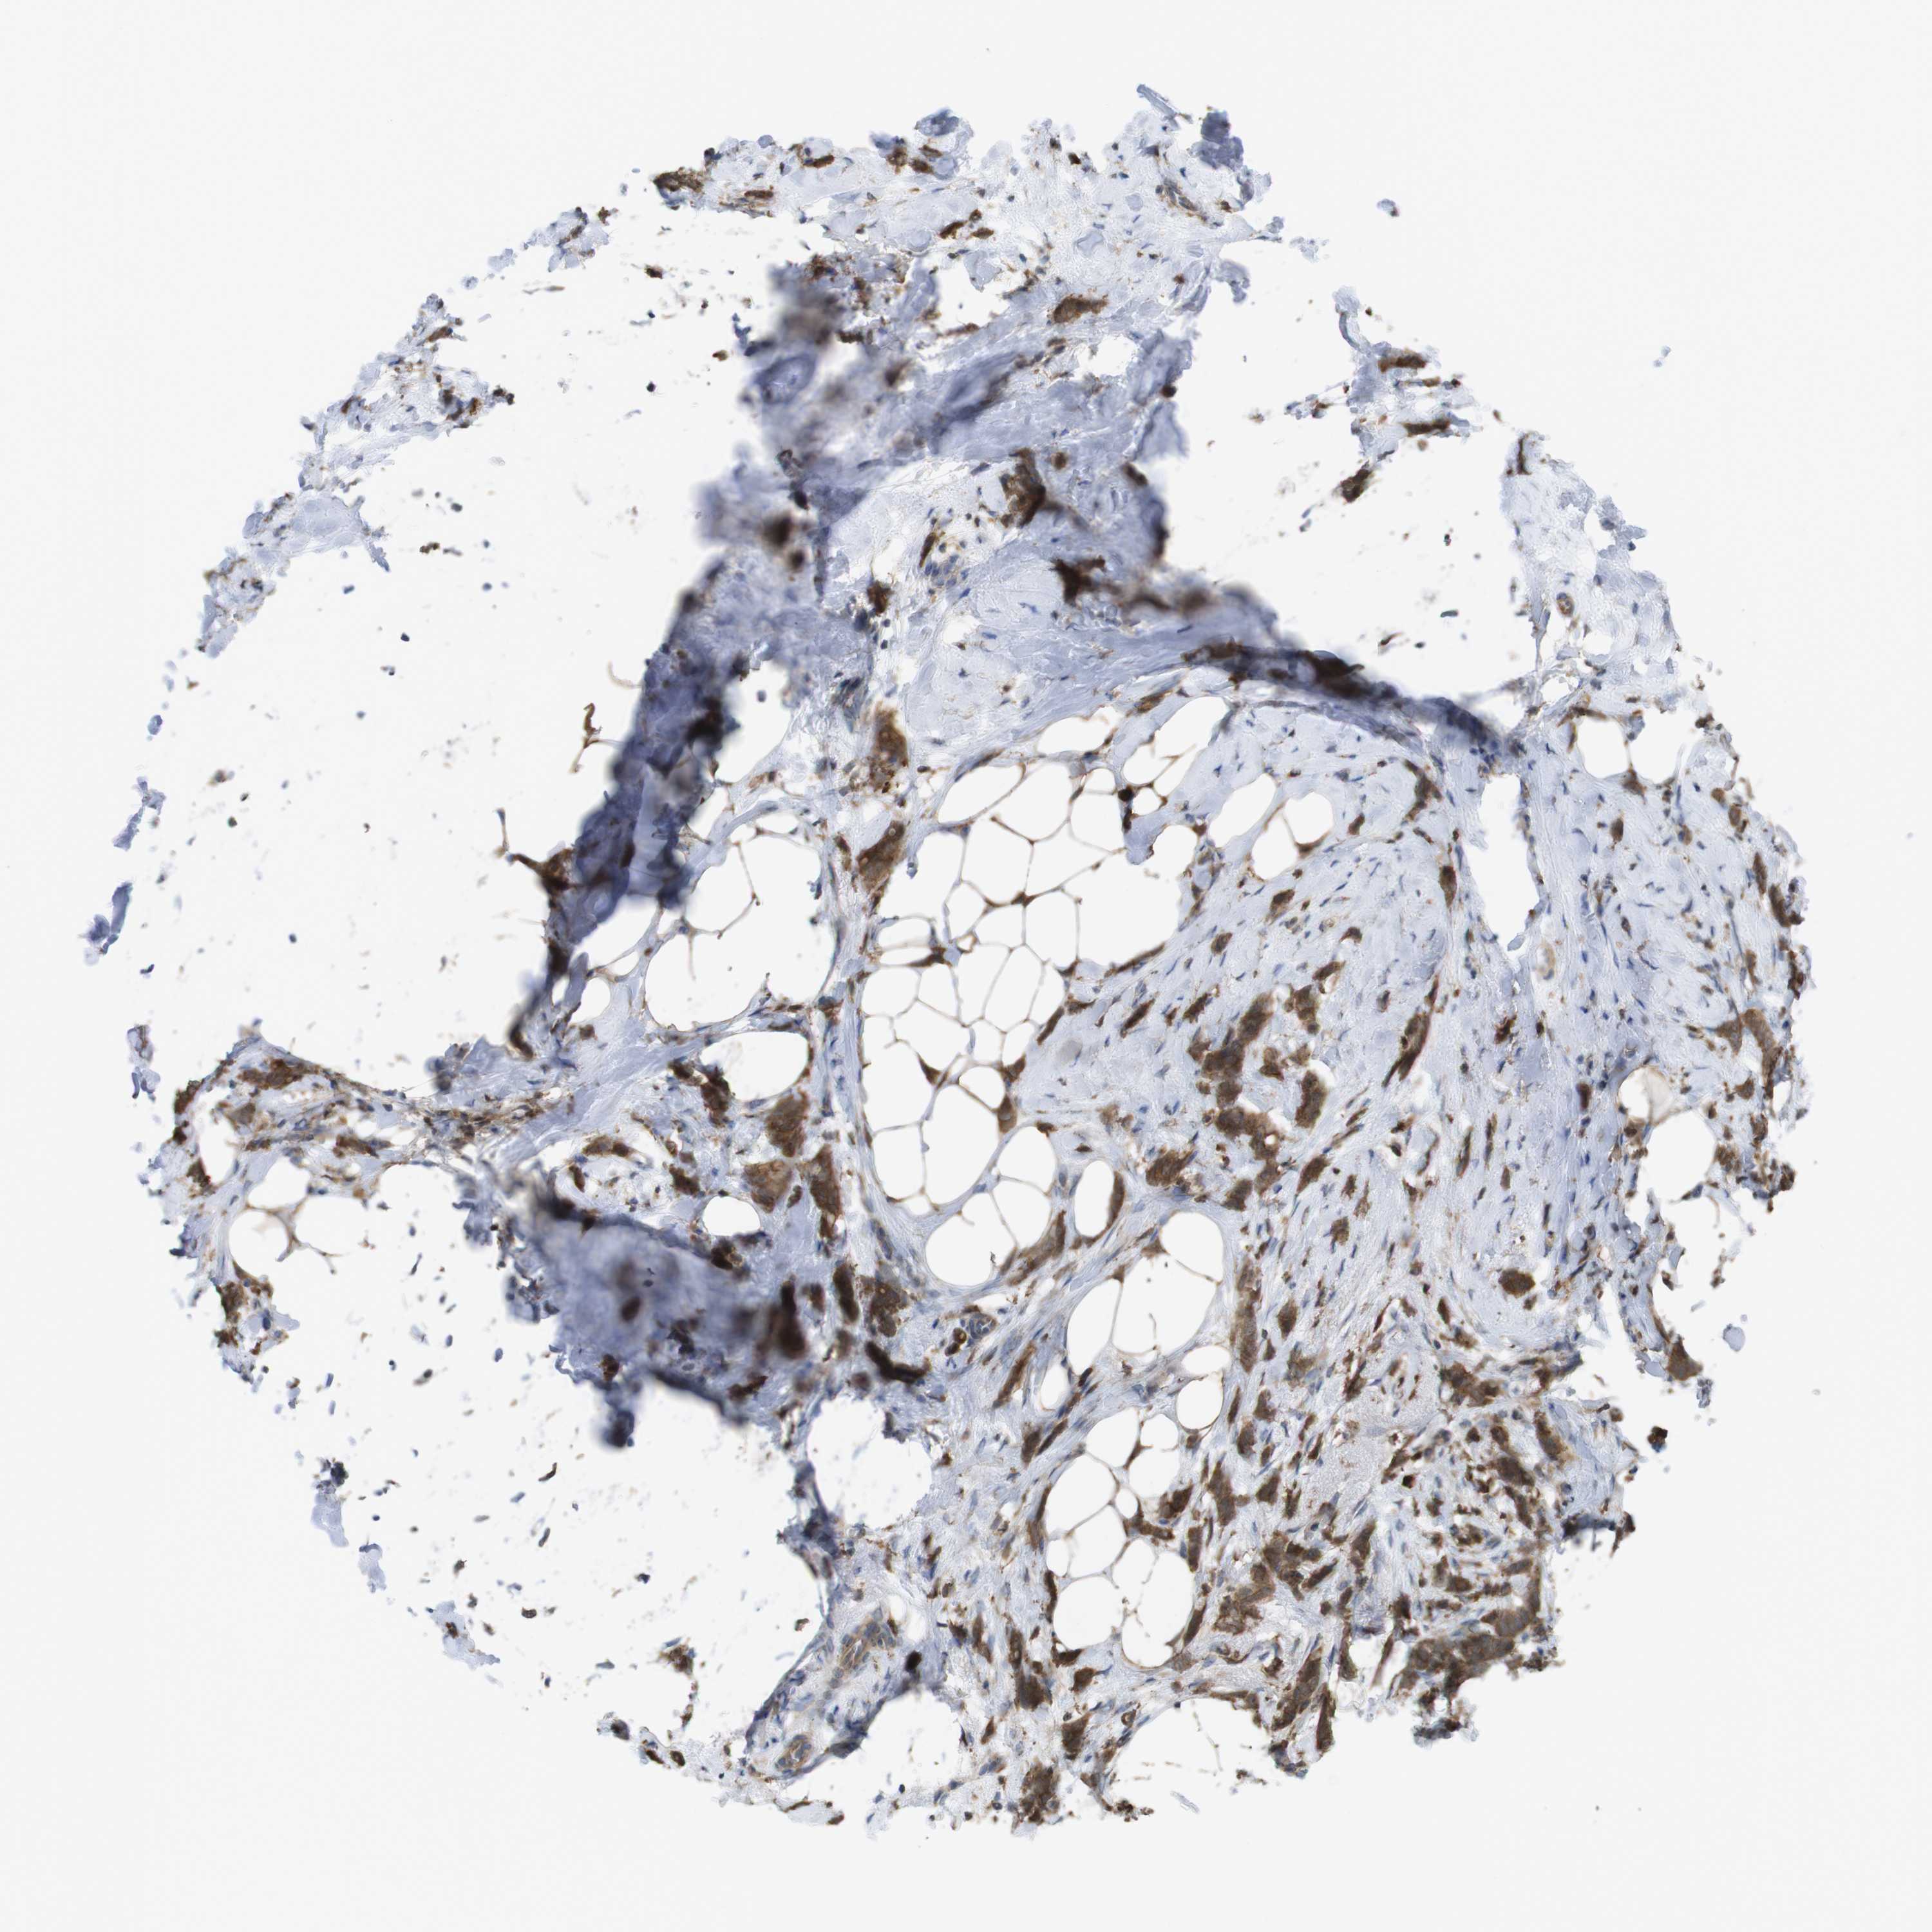

BRCA TCGA BRCA VALIDATION PROTEIN EXPRESSION